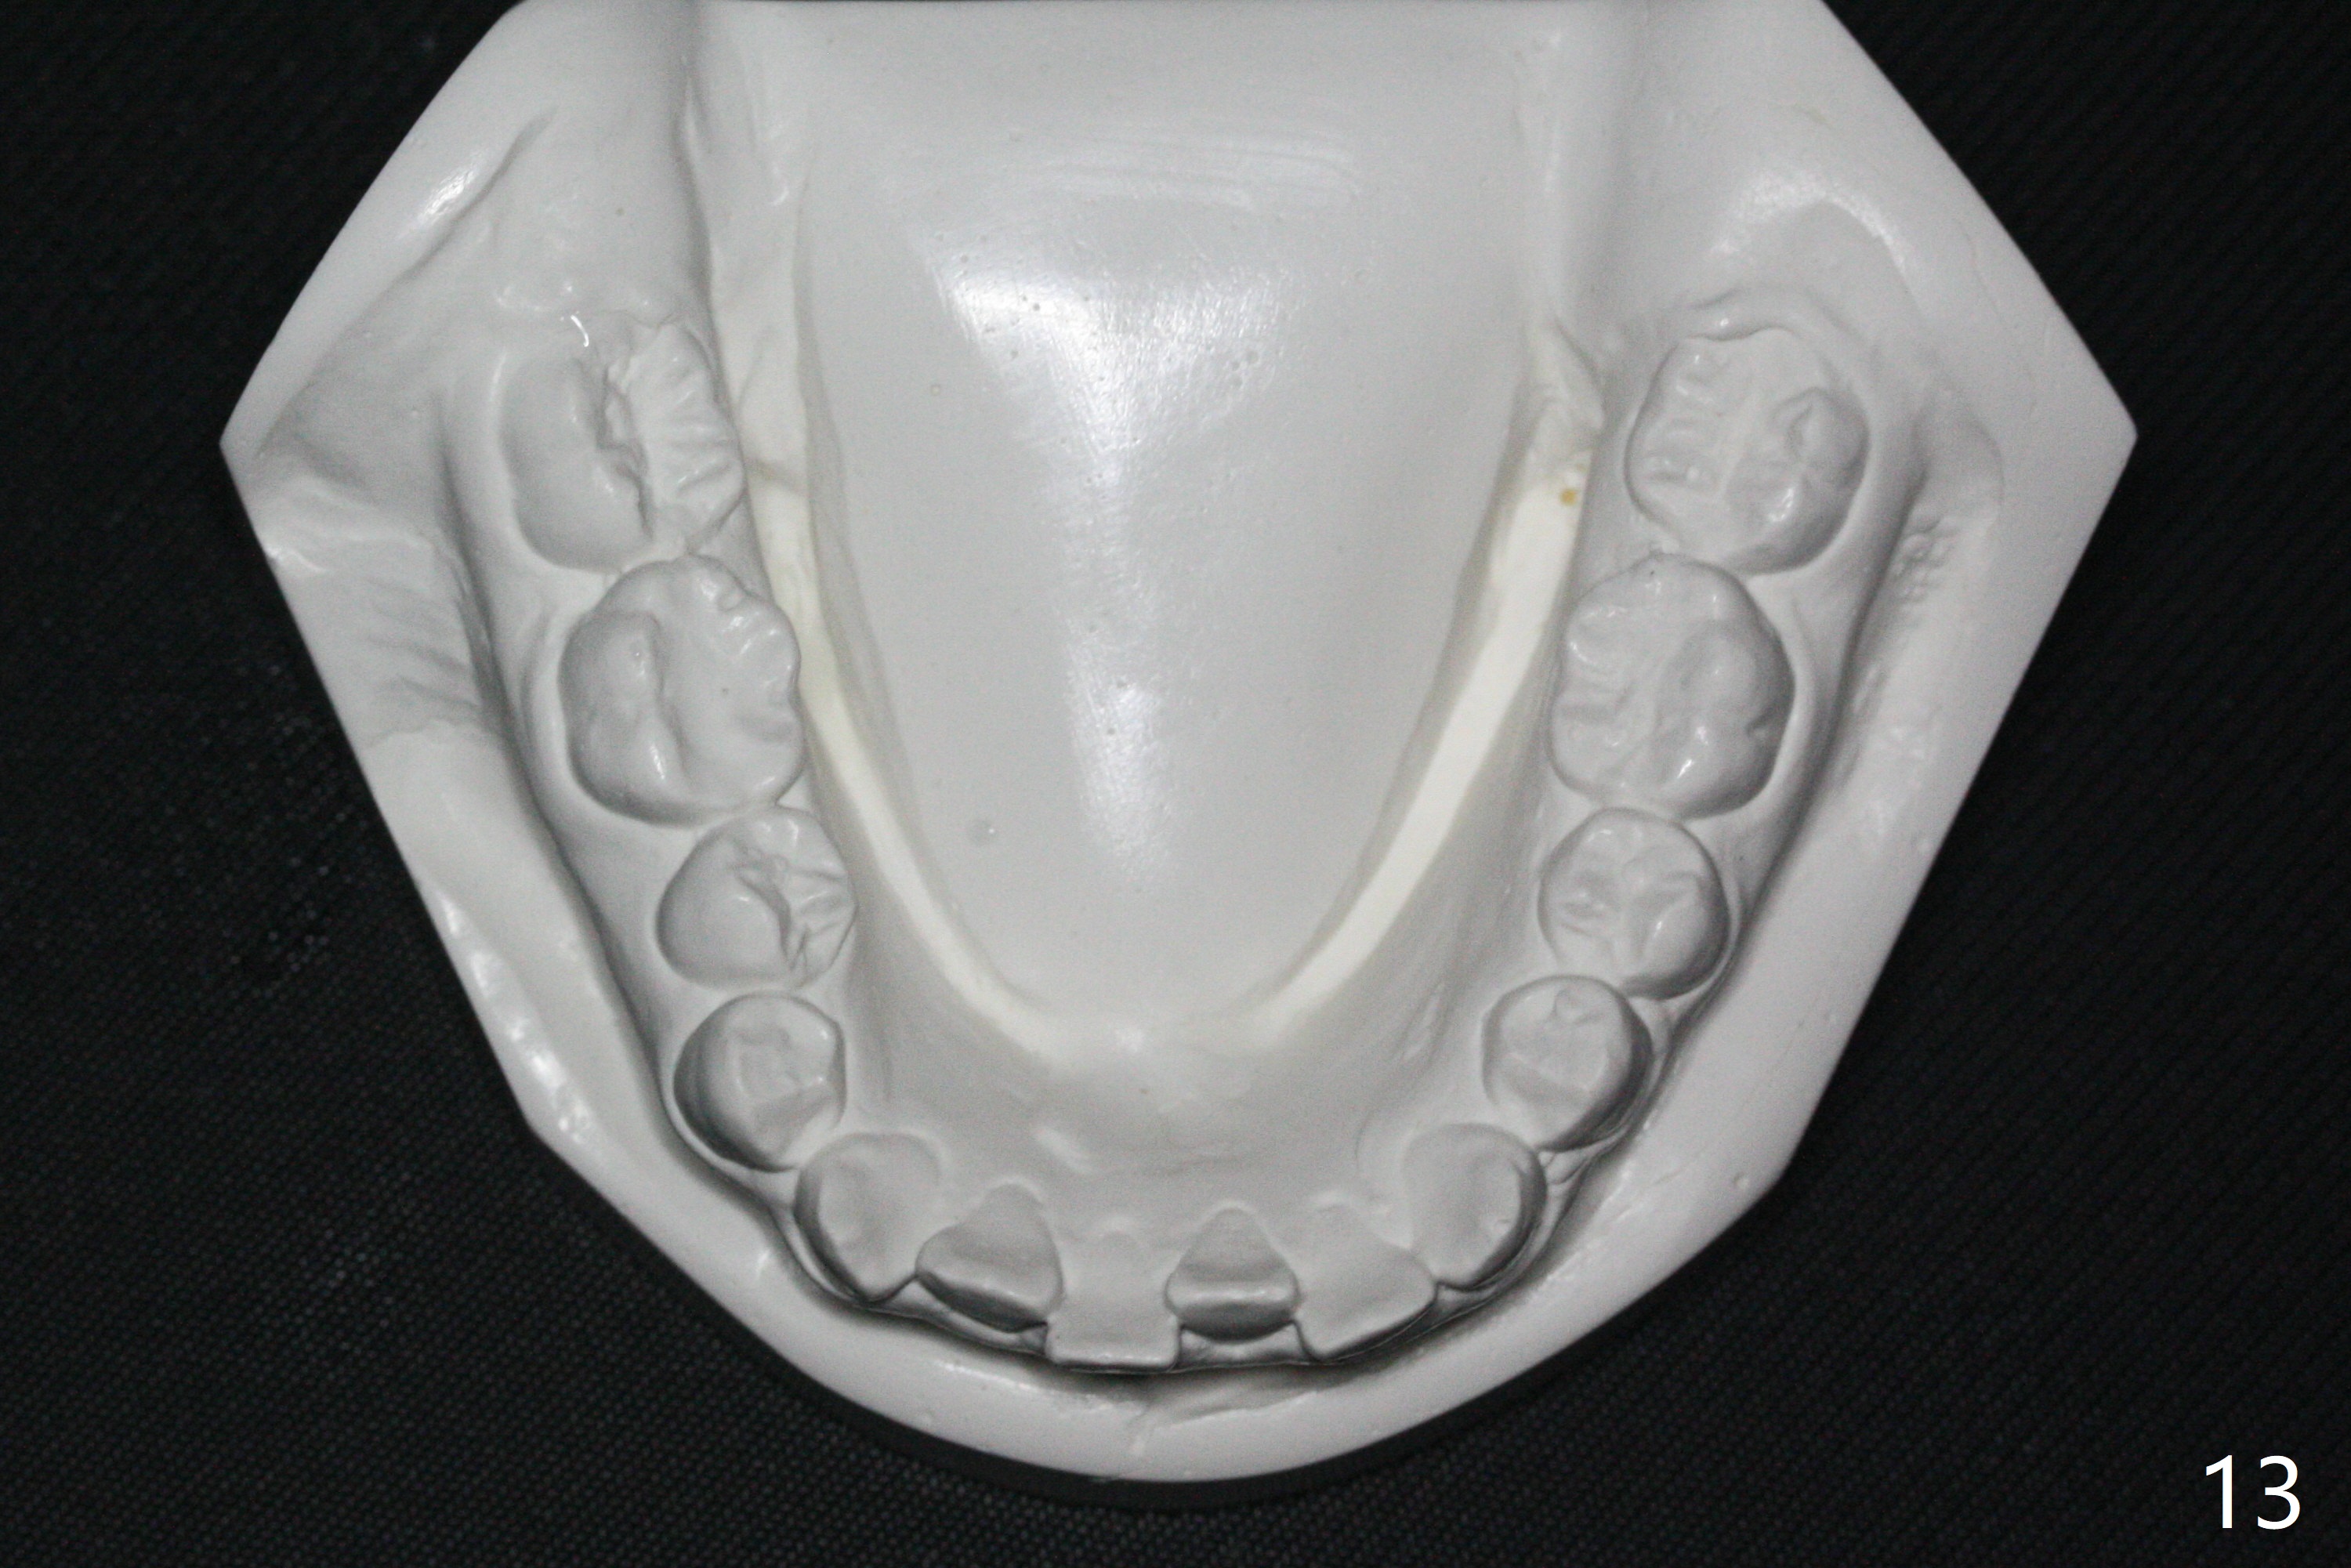

A 14-year-old woman has convex facial profile (Fig.1-4) with the upper midline shifted to the left (Fig.2). Since the roots of the 1st bicuspids are short (Fig.5), extraction should be easy. U3 will be retracted distal early with intention to correct the upper midline. With Class I occlusion at the canines and the 1st molars and good initial interdigitation (Fig.6-11), orthodontic treatment should be rewarding. Because of severe crowding (tight contact, Fig.12,13), place separators after extraction and place bands and brackets a few days later. Cephalometric analysis (Fig.14) shows that SNB is greater than SNA (82.4 vs. 81.8 degree); after extraction, retract the lower anterior teeth prior to the upper ones. It is easy to place separators after extraction (Fig.16,17).